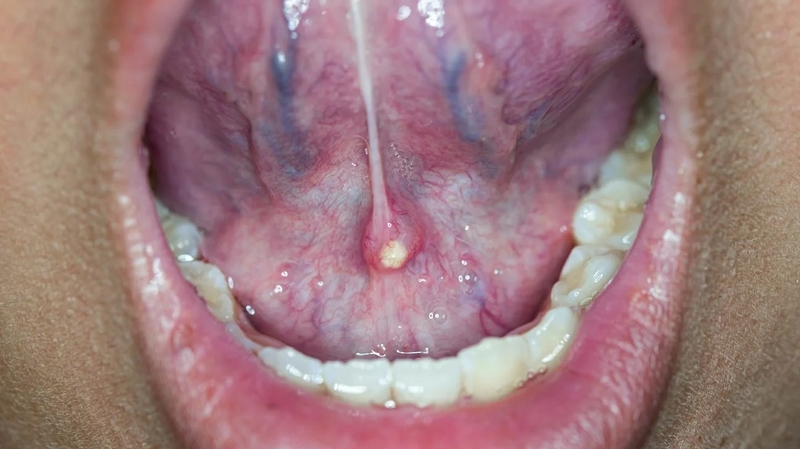

Viêm tuyến nước bọt có thể xảy ra do vi khuẩn hoặc virus gây nhiễm trùng, tắc nghẽn tuyến nước bọt. Nguyên nhân gây viêm cũng có thể do các bệnh tự miễn. Khi tuyến nước bọt bị viêm, người bệnh bị sốt, sưng đau tại vị trí viêm thậm chí có mủ chảy trong miệng. Nếu nguyên nhân gây viêm do nhiễm khuẩn, bác sĩ sẽ chỉ định dùng kháng sinh để điều trị.